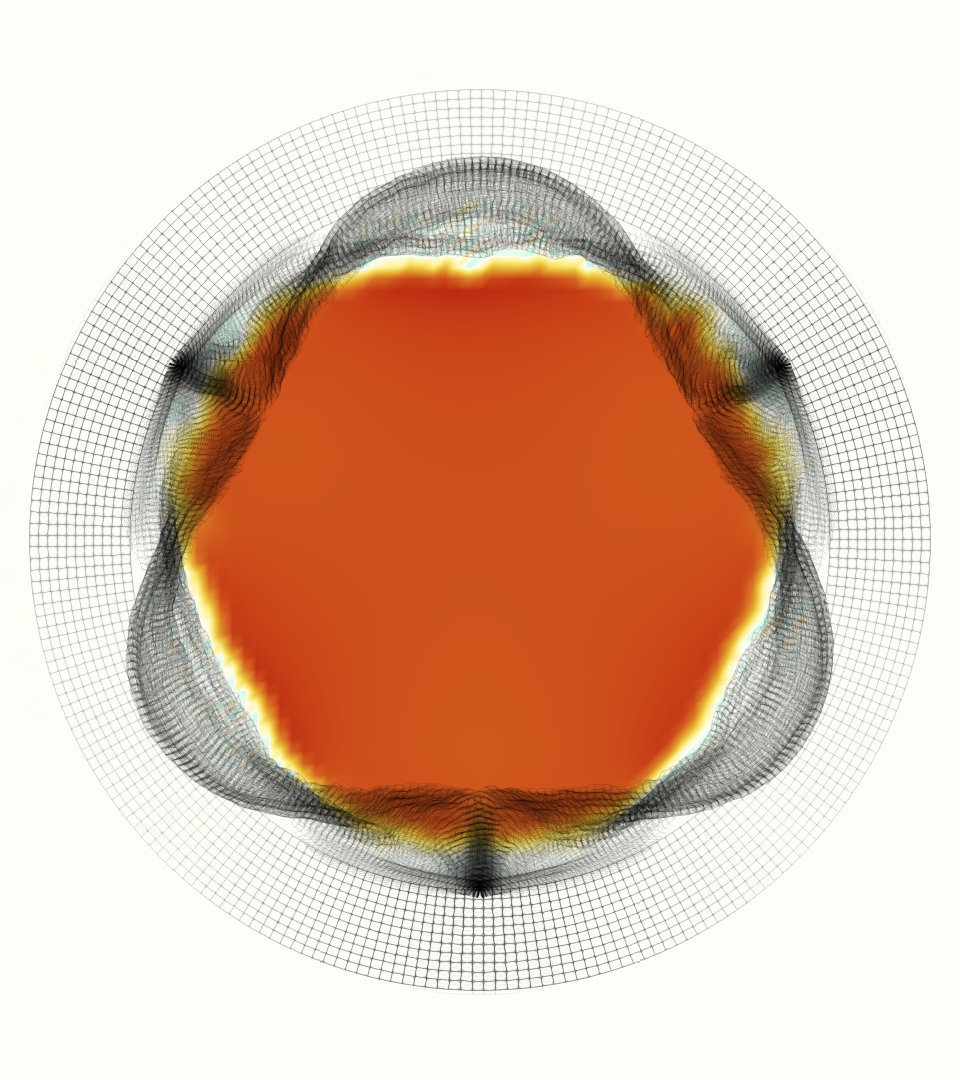

The gross morphology of the model valve that emerged from this process is shown in Figure 4. The free edge was 2.87 cm, corresponding to 3.3 cm in the predicted loaded configuration. After the pinching the leaflets together at the commissures, this left approximately 2.1 cm of free edge rest length per leaflet free to move independently of the other leaflets, within measurement error of ±0.1 cm from the free edge length of 2.2 cm measured on the prostheses. The leaflet rest height was 0.94 cm corresponding to a predicted loaded height of 1.44 cm. The measured leaflet height of 1.3 cm is nearly the predicted loaded height of 1.44 cm, which may be because the leaflets are so compliant in the radial direction, that pulling them flat to measure them achieved substantial stretches. The fiber orientation of the model runs from commissure to commissure and qualitatively matches experimental observations [38], though direct quantitative comparison is beyond the scope of this work. One minor limitation is that we do not add bending rigidity to the leaflets, beyond what emerges from the thickening process described above, and thus may not accurately capture leaflet flutter or other similar behaviors. Based on the thickness of mm, we estimated the mean tangent modulus at the predicted loaded stretches as dynes/cm2 circumferentially and dynes/cm2 radially. The prosthetic valve tissue is fixed in glutaraldehyde, and literature values for the fully-recruited circumferential tangent modulus of fixed porcine aortic valve tissue vary widely. Based on the experimental measurements of Billiar and Sacks and their constitutive law for valves fixed under 4 mmHg of pressure, we evaluated their constitutive law at the relevant stretches and and estimated the circumferential tangent modulus to be dynes/cm2 [6]. Rousseau et al. reported moduli ranging from to dynes/cm2, depending on the applied preload during fixation [36]. Sung et al. reported moduli ranging from to dynes/cm2, depending on fixation pressure [43]. Thus our estimated tangent modulus falls within the range of existing studies, so we considered our resultant modulus in good agreement given the complexity of the steps involved, phenomenological nature of the constitutive law and uncertainties in experiments. We do not have access to the precise material properties of the prosthetic valve, and further, the only literature we could find on the material properties of a similar prostheses reported the tangent modulus at one particular loading, which did not appear to be at a relevant stretch for comparisons with our model [19]. Thus, our model has material properties in a reasonable range for a fixed aortic valve prostheses (placed in the pulmonary position in our simulations), but it does not directly model the material properties of the prostheses.

We constructed the model vessel for FSI simulations from data from the MRI scans (Figure 4). The signal magnitude of 3D printed model material is distinct from the signal of the fluid in the scans, and we applied a thresholding operation to generate a three-dimensional model of the printed vessel surface. Using the MRI data ensured that the MRI and simulation coordinates were consistent in space and there were no alignment or registration errors. While using the files that generated the 3D printed model would have offered more spatial fidelity, the potential error in flow fields due to any mis-registration would have likely been much more substantial. Using Meshmixer (San Rafael, CA), we smoothed the mesh to remove stair-step effects and removed artifacts from the valve scaffold. We then remeshed to the desired edge length of 0.25 mm and extruded the model 0.25 mm and 0.5 mm to create a three-layer structure. As in the valve, this serves to eliminate the “grid aligned artifact” that can occur with pressure differences across thin membranes in the IB method [16]. Flow extenders of length 1 cm were added to the vessel at the inlet and both outlets to ensure that the normal to the vessel was aligned with the normal of the fluid box at the inlets and outlets. In FSI simulations, the vessel was held in place using target points, stiff springs of zero rest length that connect the current position of each model node to its desired position (Section 3.3). Additional linear springs are placed on each edge in the triangulated model. These springs are not meant to model a particular material and only serve to keep the vessel rigid and stationary throughout the simulation.

At = 0, the axial slice directly at the valve annulus shown in columns 1 and 2 in Figure 6, there was excellent agreement between the simulation and experiment over the cardiac cycle in the speed and shape of the jet through the valve. In both cases, the axial velocity increased as the flow accelerated during systole and the valve leaflets opened, then decreased during diastole with slight negative velocity before the valve leaflets were fully closed. The forward flow through the valve annulus did not form a full circle, but rather developed a triangular shape with a point of the triangle forming along the interior curve of the vessel, at the bottom of the axial slices. At = 0, the points of this triangular jet shape aligned with the commissures of the valve. This shape persisted during peak systole and was well-matched by the simulation.

The axial slice = 0.625 cm, shown in columns 3 and 4 in Figure 6, cut through the support scaffolding of the valve and the leaflets when they are open. In the experimental data, the shape of the jet changed as it moved downstream. A triangular shape occurred, but the points were then aligned with the middle of each open leaflet as opposed to the commissures. Those points were also more rounded than they were at = 0. The peak velocity of the jet was faster at = 0.625 cm than at = 0, as the flow accelerated through the open valve leaflets. The simulation produced these features at = 0.625 cm. The triangular shape of the jet shifted similarly, and its speed increased compared to the upstream slice. As the flow decelerated into diastole, the jet shape remained roughly triangular but diminished in intensity before disappearing after valve closure.

The jet continued to develop at = 1.25 cm, an axial slice immediately downstream of the valve scaffolding and open leaflets, shown in columns 5 and 6 in Figure 6. In the experimental data, the points of the triangular jet shape extended further towards the vessel wall. In addition, regions of reversed flow developed in the locations downstream of the commissures, resulting in curved sides to the shape of the jet. Each tip of the jet was unique, due to variations in the individual leaflets in the physical bioprosthetic valve. These variations are apparent in the velocity fields, possibly because the jet edges are similar enough cycle to cycle that irregularities are still being captured even with phase averaging. Further discussion of these features can be found in Schiavone et al. [39], which showed that the jet tip shapes occurred in different pulmonary anatomies, demonstrating that they were likely due to inherent properties of each leaflet. The leaflets in the mathematical model of the valve are identical, so these nuances in leaflet variation could not be replicated. The simulation did capture some of the extension of the tips of the jet, as they were closer to vessel wall at slice = 1.25 cm than = 0.625 cm. The curves in the triangular sides of the jet were also present in the simulation, though they were less pronounced than the experimental data. At both = 0.625 cm and = 1.25 cm, the jet shape in the simulation was smoother than the jet in experiment. It is possible that the free edges of the leaflets in the mathematical model are not fully replicating the behavior of the physical leaflets of the bioprosthetic valve, in particular the amplitude or frequency of leaflet flutter, leading to the variations seen in the jet shape at = 1.25 cm downstream of the leaflet edges. The simulation, however, does capture the key features of the triangular shape and speed of the jet. Overall, qualitative comparisons demonstrated that the simulation reproduced key features of the flow during systole and diastole.

The phase-averaged, resampled velocity fields during peak systole and flow rates at each resolution are shown in Figure 10. Despite the limitations discussed above, we observe similar qualitative trends in the flow field at all resolutions. At all resolutions, a jet formed and angled up downstream of the valve orifice, as shown in the sagittal view. The jets showed a triangle-like cross section at with points aligned with the commissures. At cm, the jet appears like a rounded triangle in the opposing orientation, with its points aligned with the center of the leaflets. At cm, the jet is narrower downstream of the commissures, and wider downstream of the leaflets, again with a triangle-like cross section. The area of the jet increased with resolution, as expected given the IB method thickening of the valve structure. The narrowed jets at the two more coarse resolutions show locally elevated velocities relative to the two more fine resolutions. Figure 11 shows the instantaneous velocity fields at each resolution in the same axial and sagittal views. At 0.9 mm, the sagittal view shows a qualitatively different jet than at finer resolutions, with regions of lower velocity farther from the vessel wall, indicating insufficient resolution. At 0.9 and 0.68 mm, the jet is visibly narrowed compared to higher resolutions. While some features are similar at these two coarse resolutions, we conclude that the narrower jets indicate these simulations are under-resolved. Flows in the three finest resolutions, 0.45, 0.34 and 0.28 mm. appeared qualitatively similar, with slightly more fine structure detail in both the axial and sagittal views present at the edges of the jet. The jets in the axial views all showed a similar triangle-like cross section, slightly narrower downstream of the commissures, as in the phase-averaged fields. In both the phase-averaged and instantaneous fields, the three finest resolutions appear sufficiently similar that the conclusions of this study would be identical with any of these resolutions.